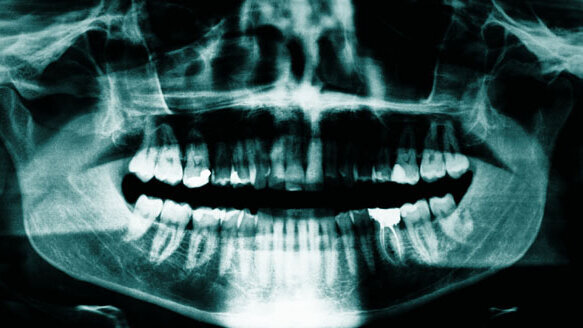

GROOT-BIJGAARDEN, BELGIË – Meer dan de helft van de röntgenfoto's die Belgische tandartsen nemen, zijn overbodig. Dat concludeert het Belgische Rijksinstituut voor ziekte- en invaliditeitsverzekering (RIVIZ) in de Vlaamse krant Het Nieuwsblad.

Het RIVIZ analyseerde 5.500 röntgenfoto’s en concludeerde dat 56% ervan overbodig was. De kosten van die foto’s zijn zo'n 11,34 miljoen euro per jaar. Bij nog eens 21% was het twijfelachtig of ze van nut waren.

Slechts 22% van de röntgenfoto's bleek echt nut te hebben. Die foto’s worden bijvoorbeeld gebruikt om implantaten te controleren of verborgen aandoeningen aan licht te brengen.

Volgens Stefaan Hanson van het Verbond der Vlaamse Tandartsen overdrijft het rapport met de term ‘overbodig’. "Tijdens het eerste bezoek van een nieuwe patiënt is een scan heel leerrijk. Bovendien zijn röntgenfoto's vooral in Wallonië populair, de Vlaamse tandartsen houden veel meer rekening met de risico's van straling,” aldus Hanson. (bron: Het Nieuwsblad)